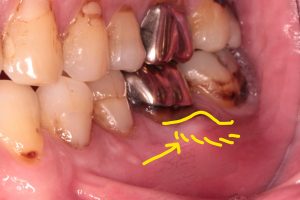

この症例は左下が腫れたということで当医院に来院された方です。

写真を見てみると下顎左側第一大臼歯

つまり奥から2番目の銀歯の横の歯ぐきがぷくっとしているのが分かります。

さて、クラウン(銀歯)を外して実際にパーフォレーションを直視下で確認していきます。

やっぱり近心根の根分岐部にパフォーレーション(歯の穿孔)が見つかりました。軟化象牙質を丁寧に除去していくと結構な大きさになりました、